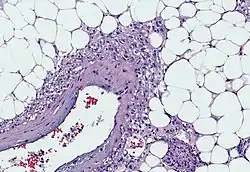

- Myoid cells with clear cytoplasm spinning off of large vessels in a background of mature fat, the classic microscopic features of angiomyolipoma